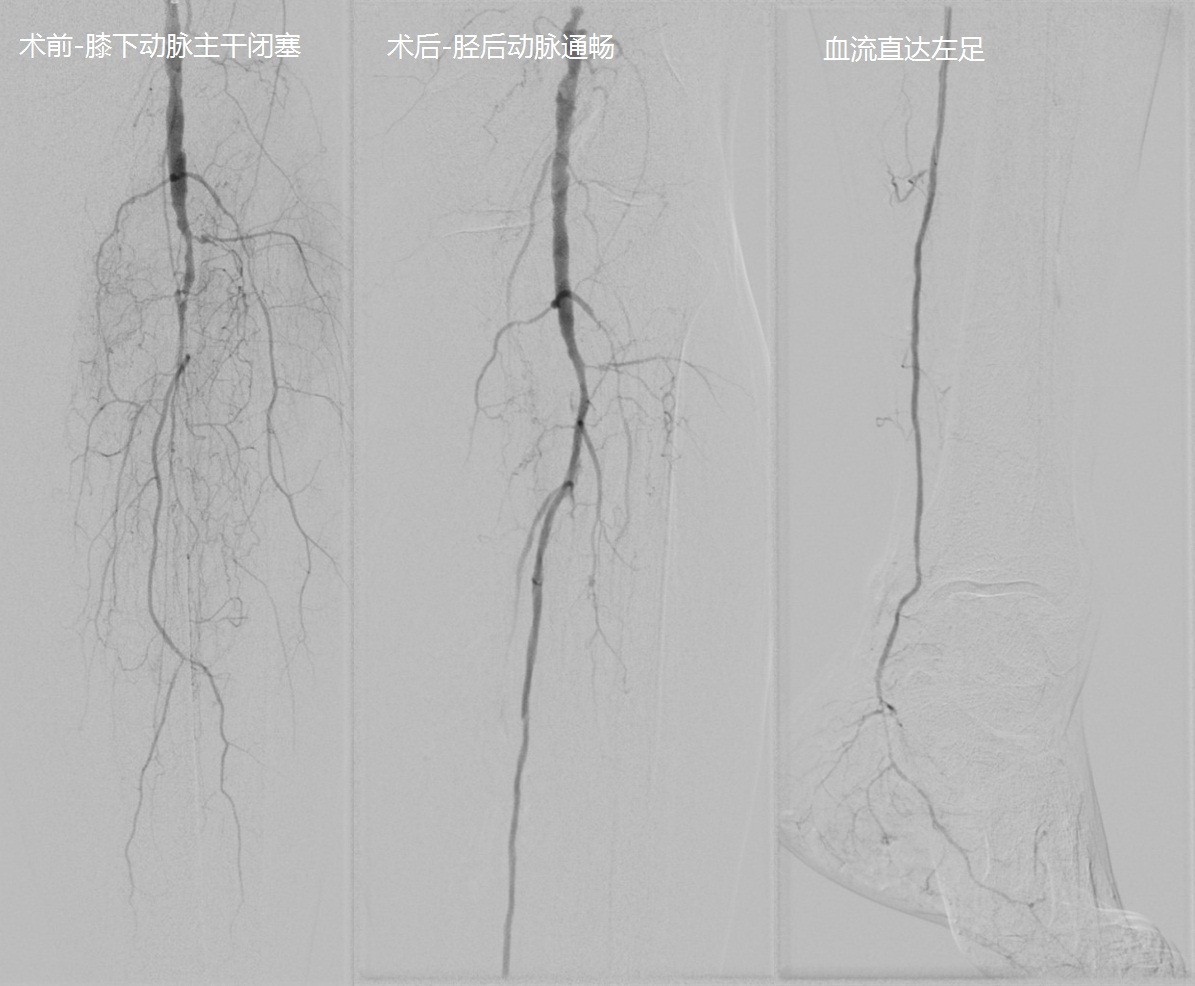

患者孟妈妈75岁,罹患糖尿病30余年,但一直没有规范服用降糖药、监测血糖,打胰岛素也是隔三差五、随心所欲根本不按剂量来。由于糖尿病周围神经病变,四肢对冷热疼痛等感觉都不灵敏,3个月前由于新鞋大小不合适,挤压了左脚第4足趾,造成足趾侧面破溃,迁延不愈。家人将孟妈妈送来北京清华长庚医院血管外科。吴巍巍主任团队经过仔细评估,发现孟妈妈左侧膝盖以下3支动脉主干皆闭塞,只留左侧胫后动脉远端存留纤细一段,借助B超引导下穿刺,成功逆向开通胫后动脉,恢复足部血运,帮助溃疡愈合,避免创面不断扩散最后不得不截肢保命的结局。

4胫后动脉介入手术开通前后对比